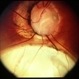

- coloboma

- MEHUL SHAH

- Photo slit lamp biomicroscope

- 35-year-old male presented with diminished vision. On examination he was having nuclear sclerosis and lens coloboma.